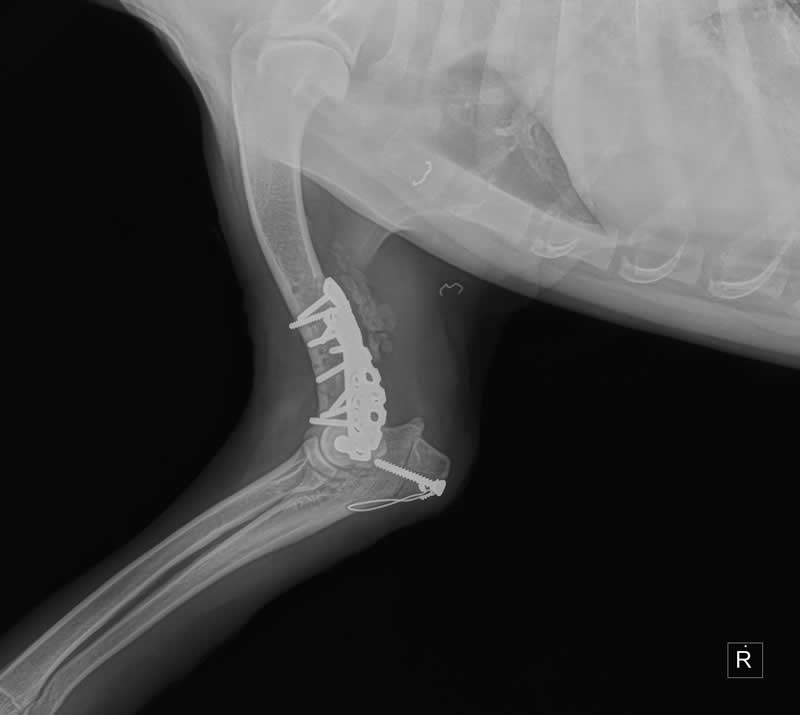

Orthopedic procedures focus on treating injuries and conditions affecting your pet’s bones, joints, and ligaments. These surgeries help restore mobility, reduce pain, and improve your pet’s quality of life. Common orthopedic procedures include fracture repairs, cruciate ligament repairs, patella luxation correction, and femoral head ostectomy (FHO).

Whether your pet has suffered an injury or is experiencing joint-related issues, our expert surgical team provides advanced, affordable orthopedic care to help them move comfortably again. We use the latest techniques to ensure a safe and smooth recovery.